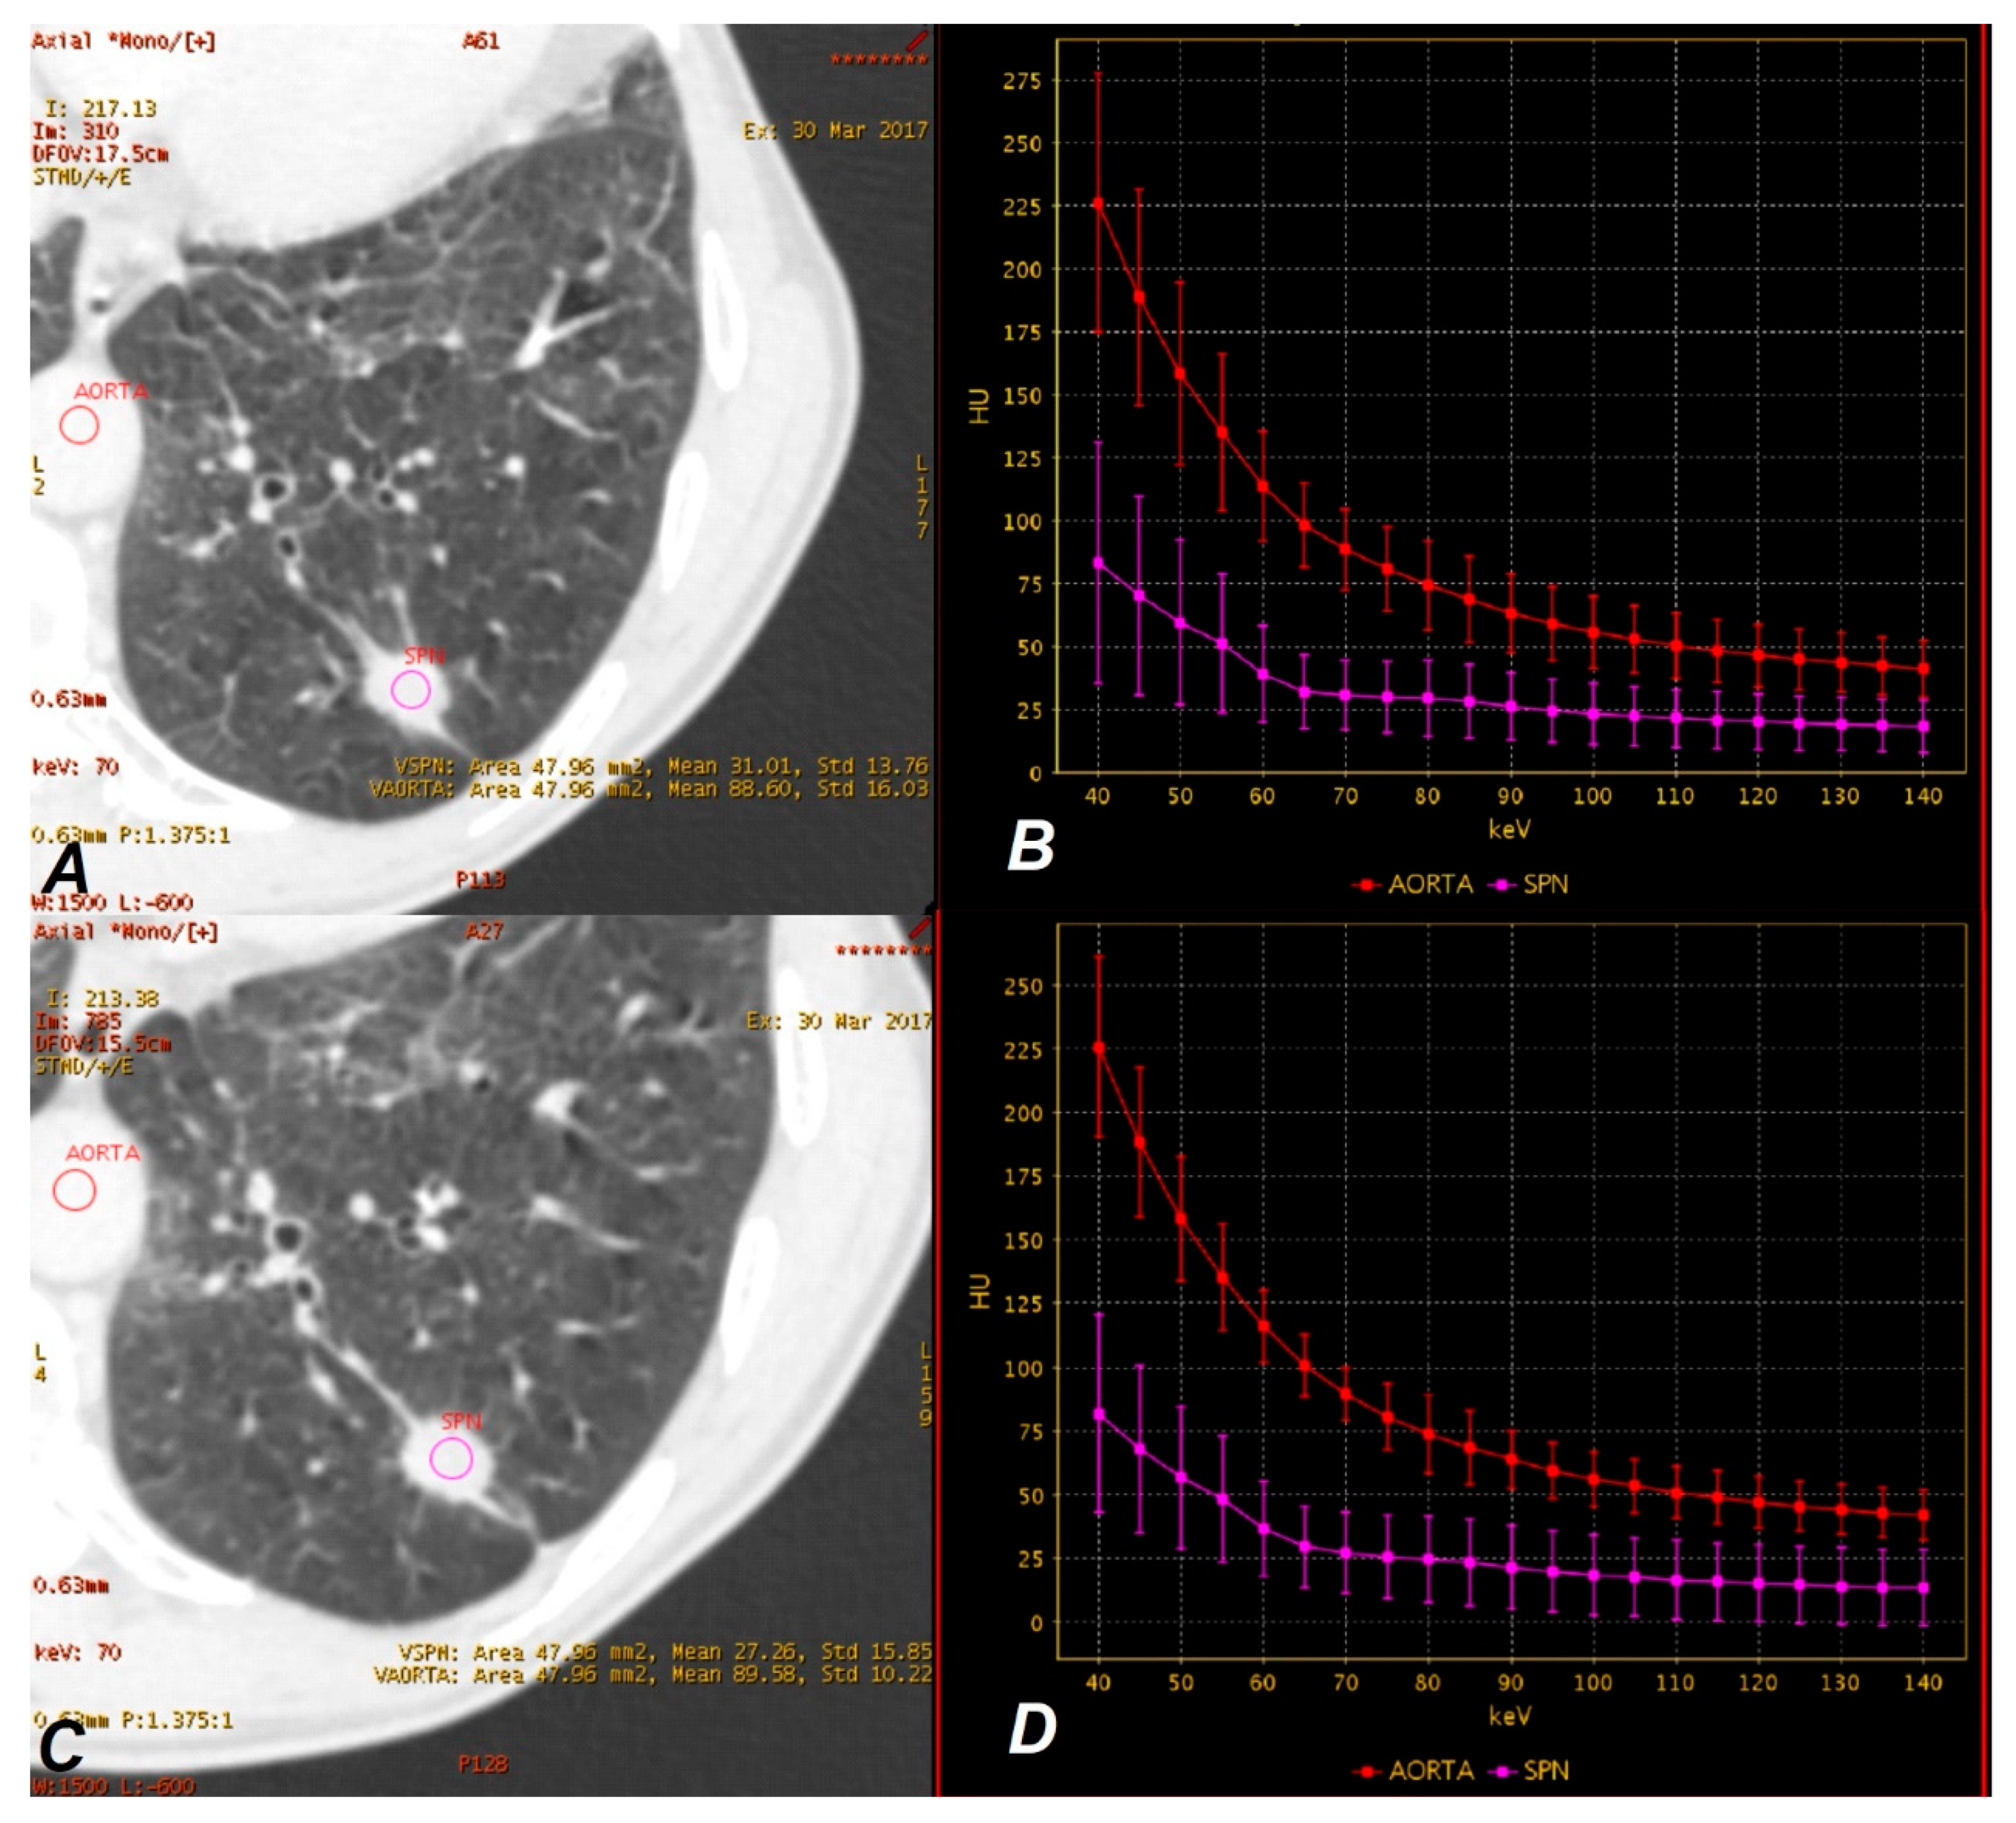

3.4. Results of the VMS Analysis

3.5. Results of the IC Map Analyses